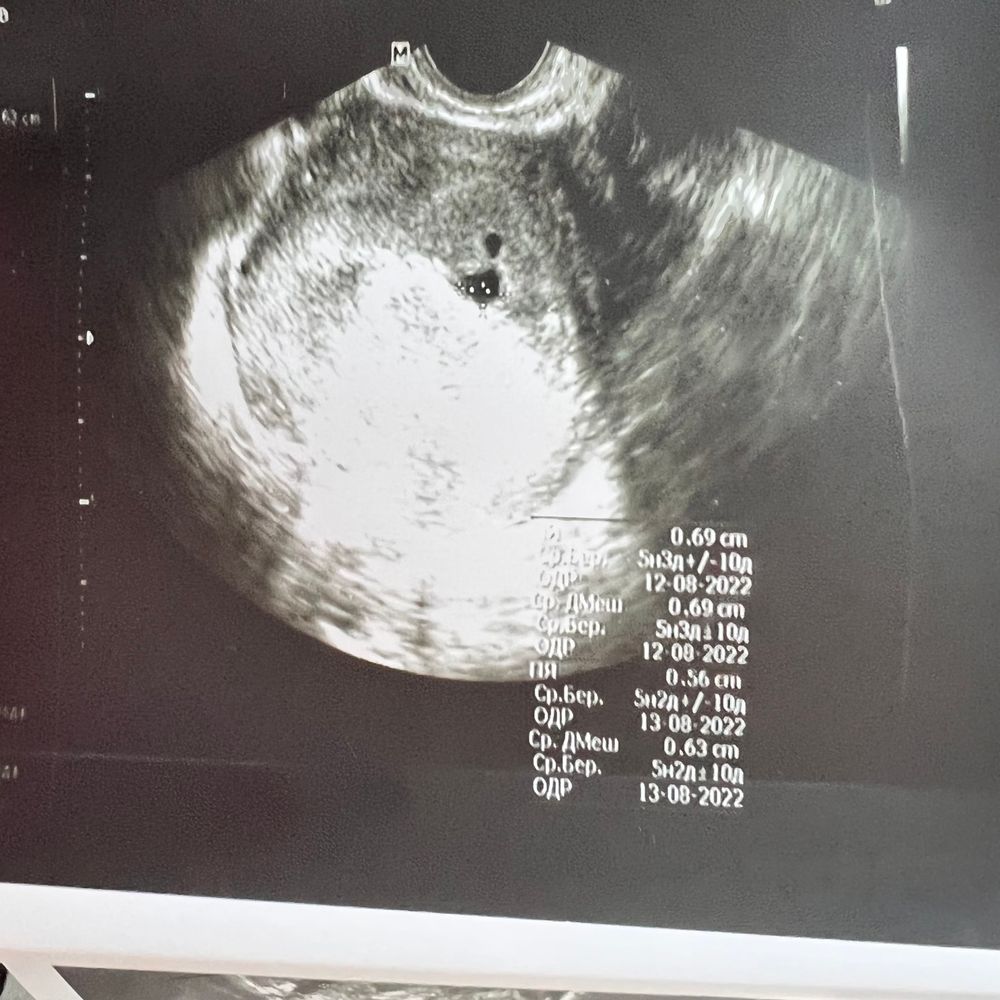

Узи 5 неделя с включениями

Может у вас двойня?)

Tatiana, ох было бы хорошо))) но врач говорил что под вопросом : киста/отслойка

У меня так было, оказалась двойня 😁